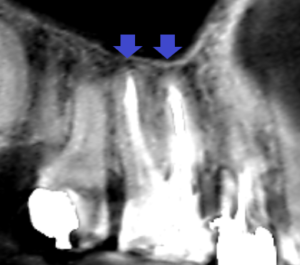

同じく上顎第一大臼歯の口蓋根の冠状断のCT画像です。

矢印の先に膿の影がみられます。